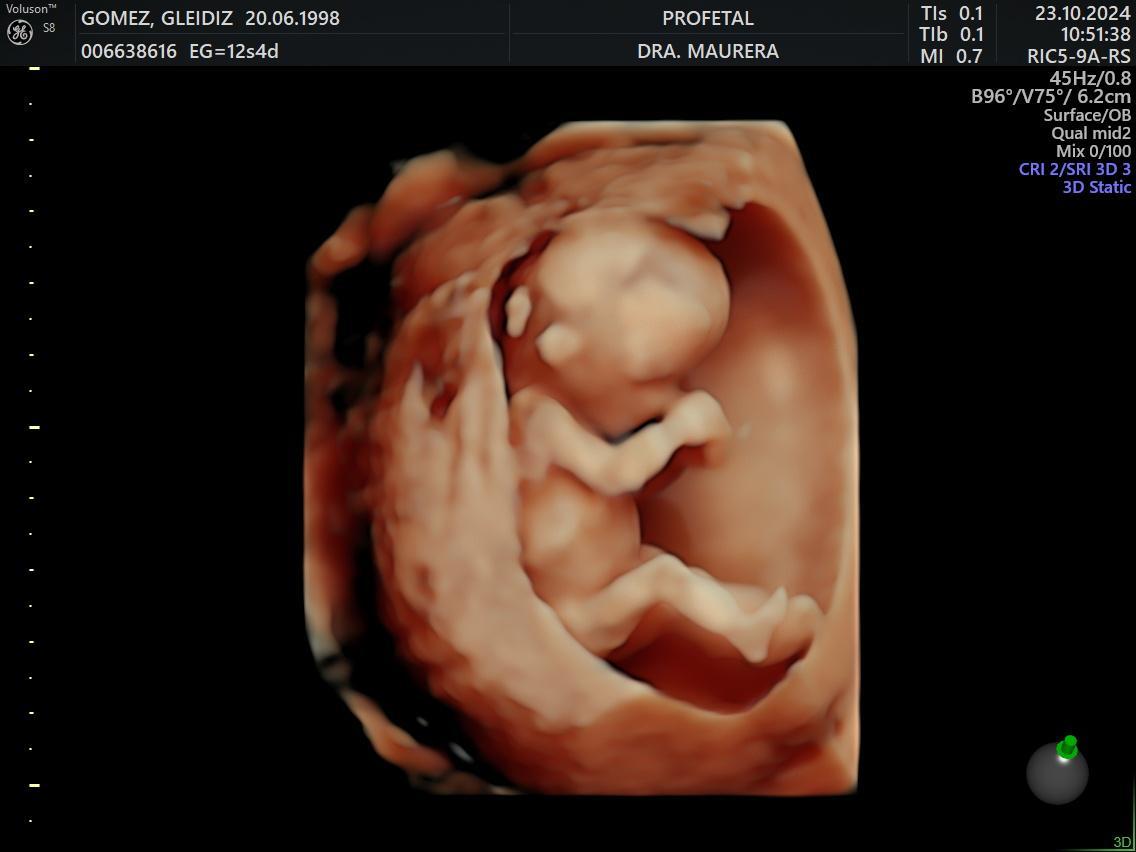

• Ecografía de Viabilidad (Semanas 4-11): Un examen transvaginal para confirmar la progresión normal del embarazo y el número de embriones. Es crucial para mujeres con sangrado, dolor, o antecedentes de abortos y embarazos ectópicos.

• Ecografía Genética Doppler (Semanas 12-14): Permite fijar la edad gestacional, diagnosticar embarazos múltiples y anomalías fetales, y evaluar el riesgo de Síndrome de Down, preeclampsia y parto prematuro.